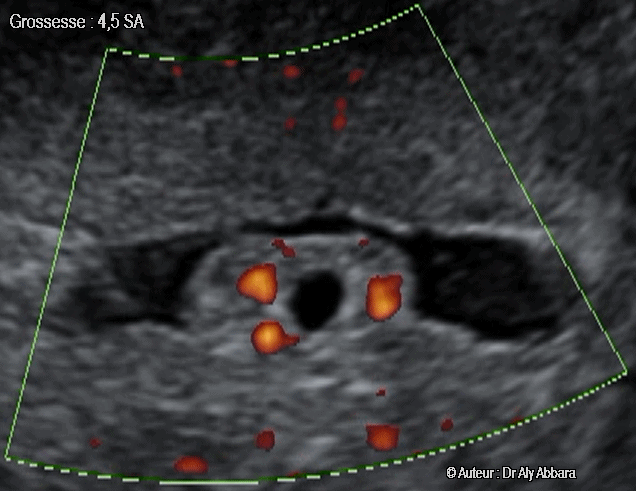

| Image échographique en GIF animée montrant une grossesse débutante intra-utérine de 4,5 SA Sur cette image on observe la présence d'un sac gestationnel de 4 mm de grand axe, sans image embryonnaire et entouré par une couronne trophoblastique. Il est implanté dans la couche superficielle de l’endomètre. Une néovascularisation péri-trophoblastique est mise en évidence sur cette vidéo grâce au Doppler "Energie". حمل داخل الرحم في بداياته الأولى و بسن الأربع أسابيع والنصف من إنقطاع الطمث (أو اليوم 17 بعد الإلقاح) |